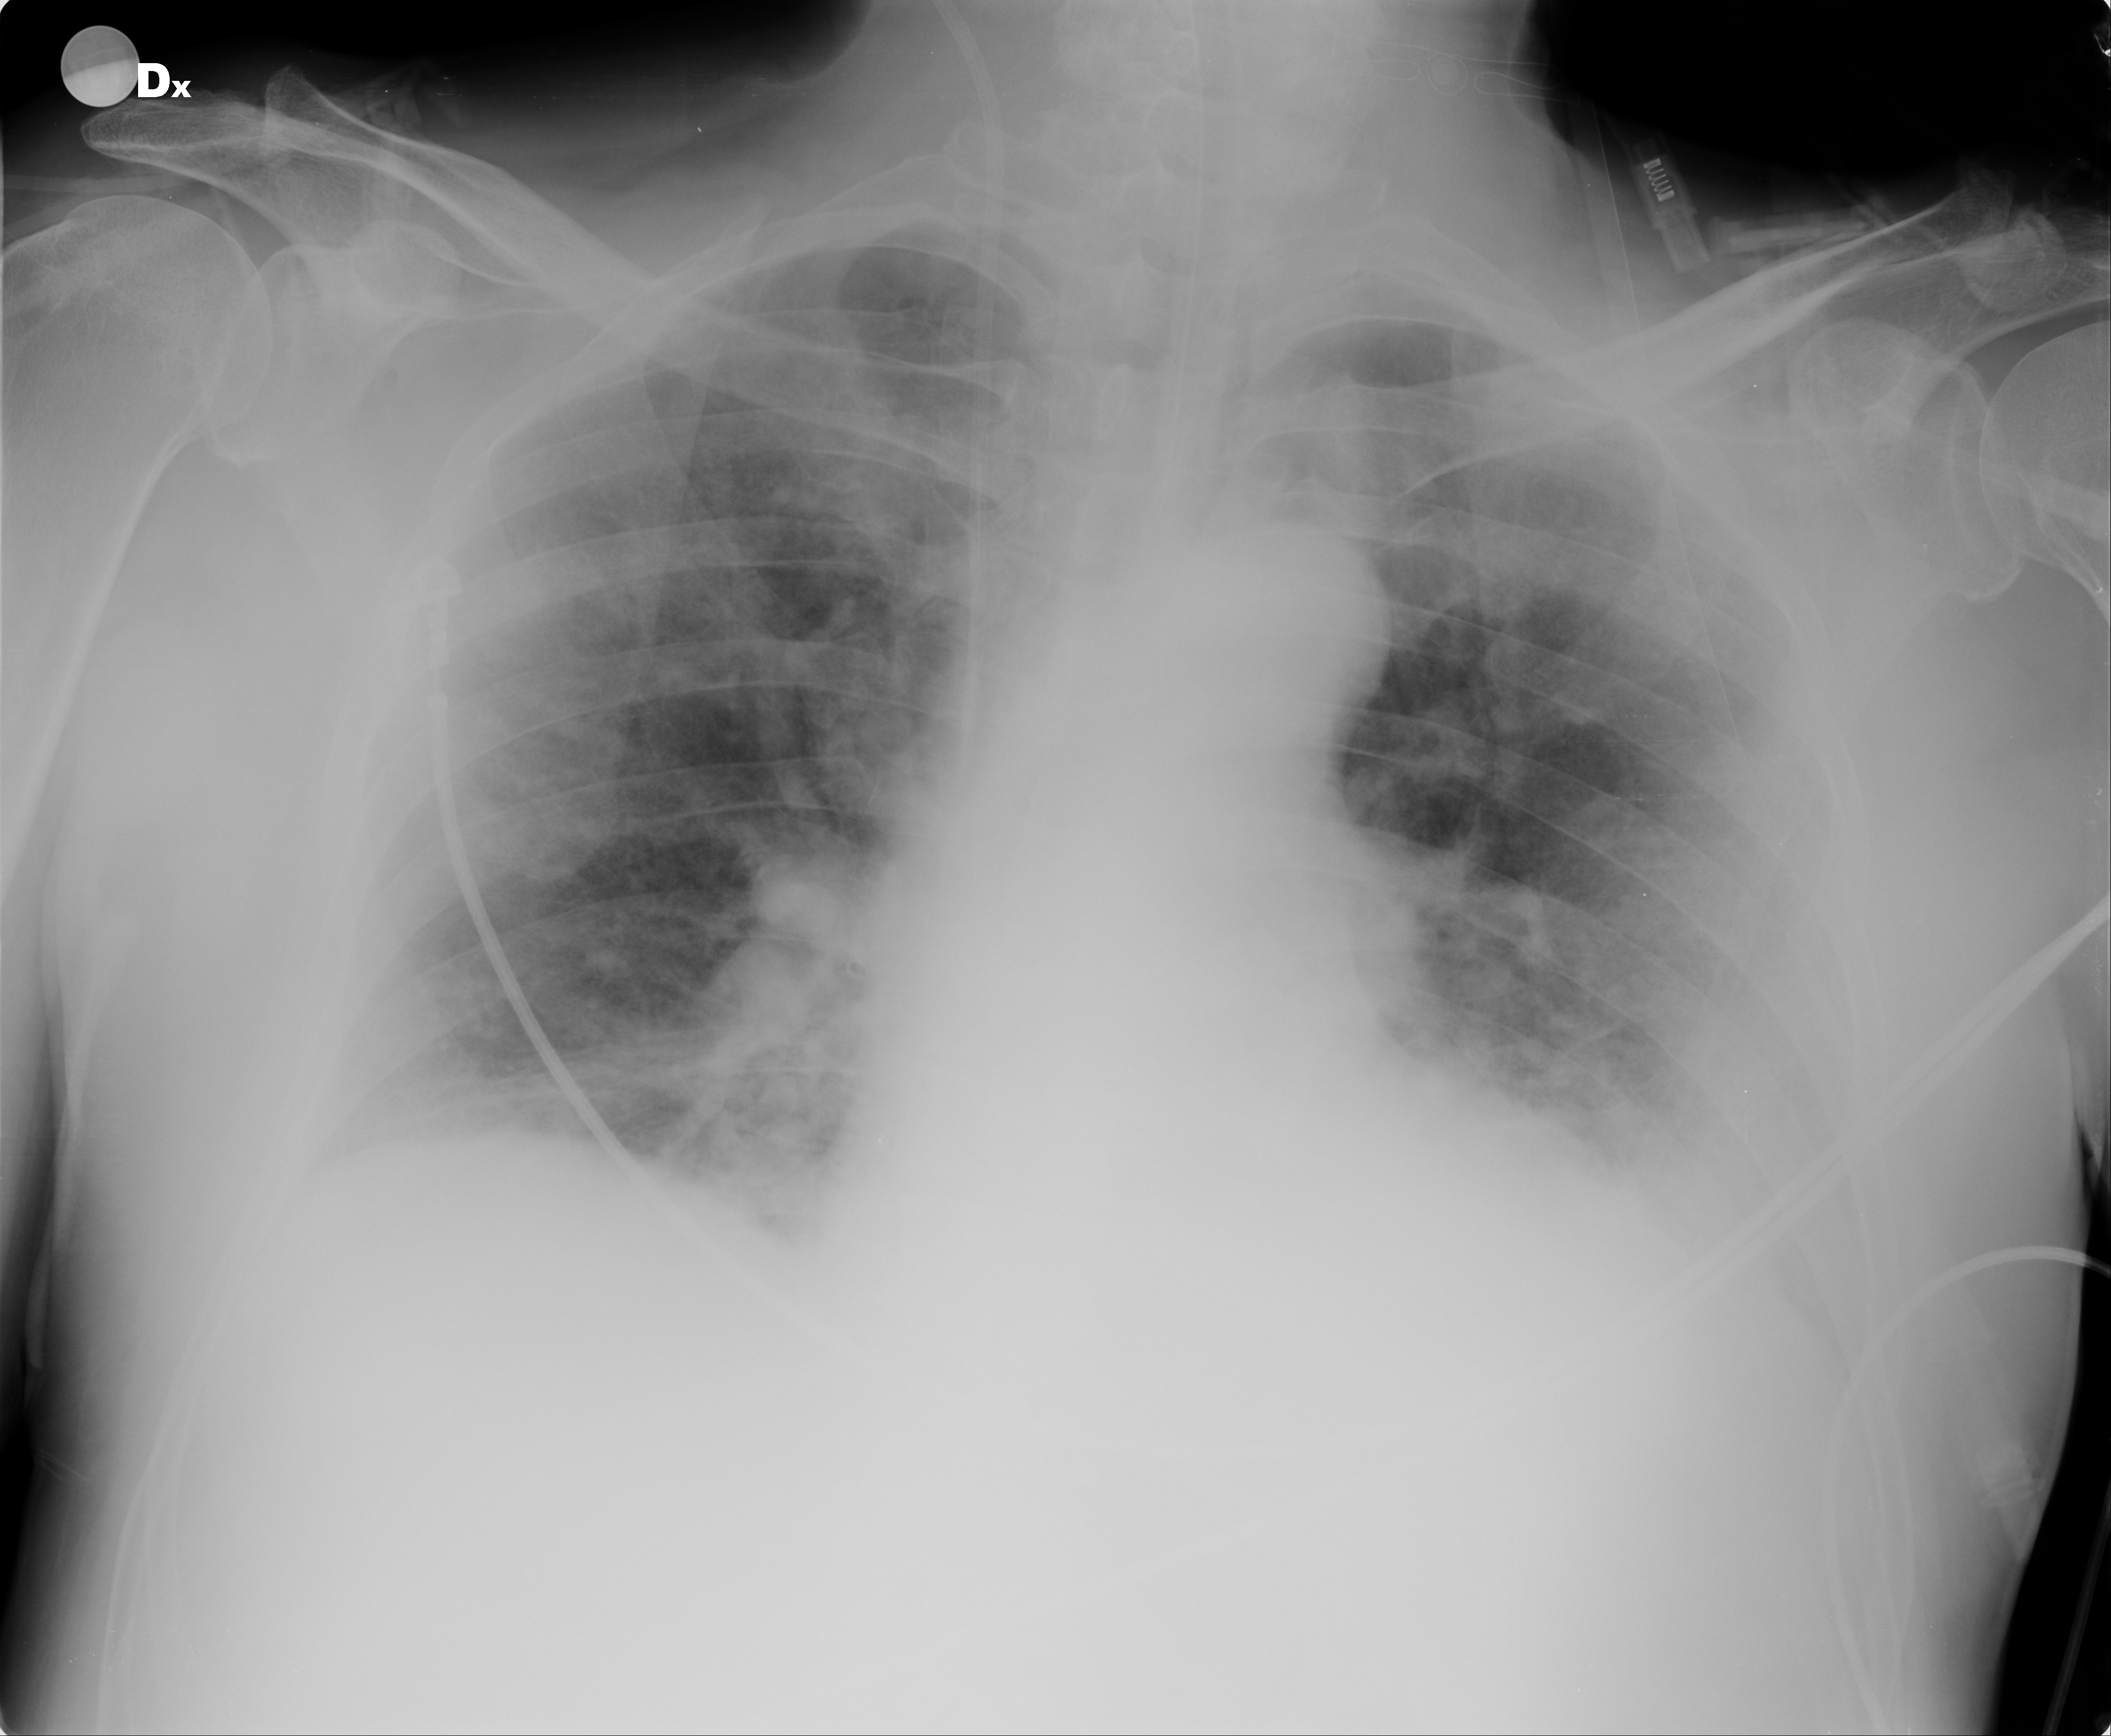

We employ a large-scale of chest X-ray dataset COVIDx [20] to validate the proposed model. It is comprised of 18,543 chest radiography images across 13,725 cases. Example chest X-ray images belonging to normal, pneumonia, and COVID-19 classes from COVIDx dataset are shown in Figure 2. When we examine these examples, we can differentiate these images in terms of features shown within areas marked by the blue circle since we can observe some lighter areas indicating COVID-19 infected regions in the blue circle.

III-D4 Error Analysis

Fig. 6 presents three COVID-19 samples that are classified into Normal, COVID-19, and Pneumonia classes, respectively. X-ray images of COVID-19 patients shows various features for different stages of COVID-19 patients222https://www.uclahealth.orgradiologycovid-19-chest-x-ray-guideline. At the early stage of COVID-19 patients, X-ray images cannot present significant features (Fig. 6 (a)) that can be used to differentiate COVID-19 and Non COVID-19 patients, which leads to the incorrect classification result for the sample. It is consistent with the expectation that X-ray images are not ideal evidences to support diagnosis of COVID-19 for the patients at the early stage.

However, with development of COVID-19, X-ray images are able to present obvious features such as multifocal lung airspace opacities, nodules and consolidation (Fig. 6 (b)), which contributes to the correct classification result. Unfortunately, if the patients are at the late stage of COVID-19, X-ray images presents lobar diffused consolidation (See Fig. 6 (c)) that is similar to features of pneumonia. These features will be confusing to the proposed model and lead to the incorrect result for the sample shown in Fig. 6 (c). In summary, in terms of samples shown in Fig. 6, the proposed model will be effective for the patients who are in the development of COVID-19 rather than those at the early stage or late stage of such disease.